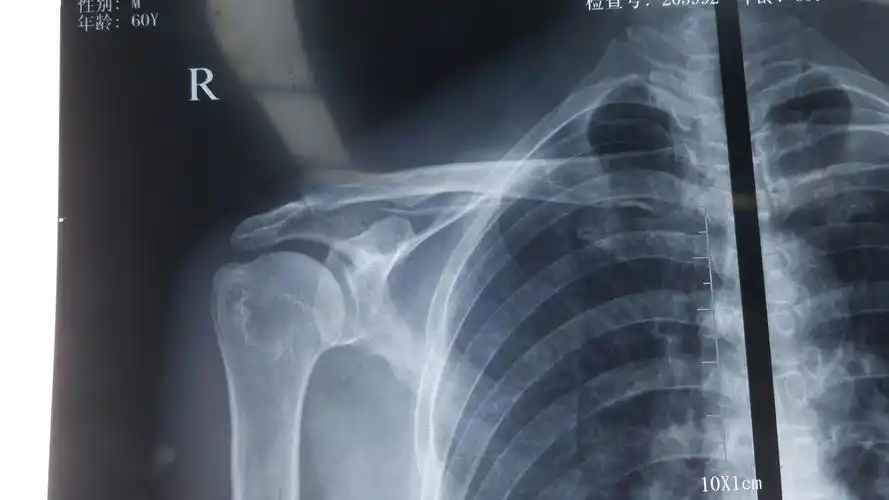

肩关节x光片 正常